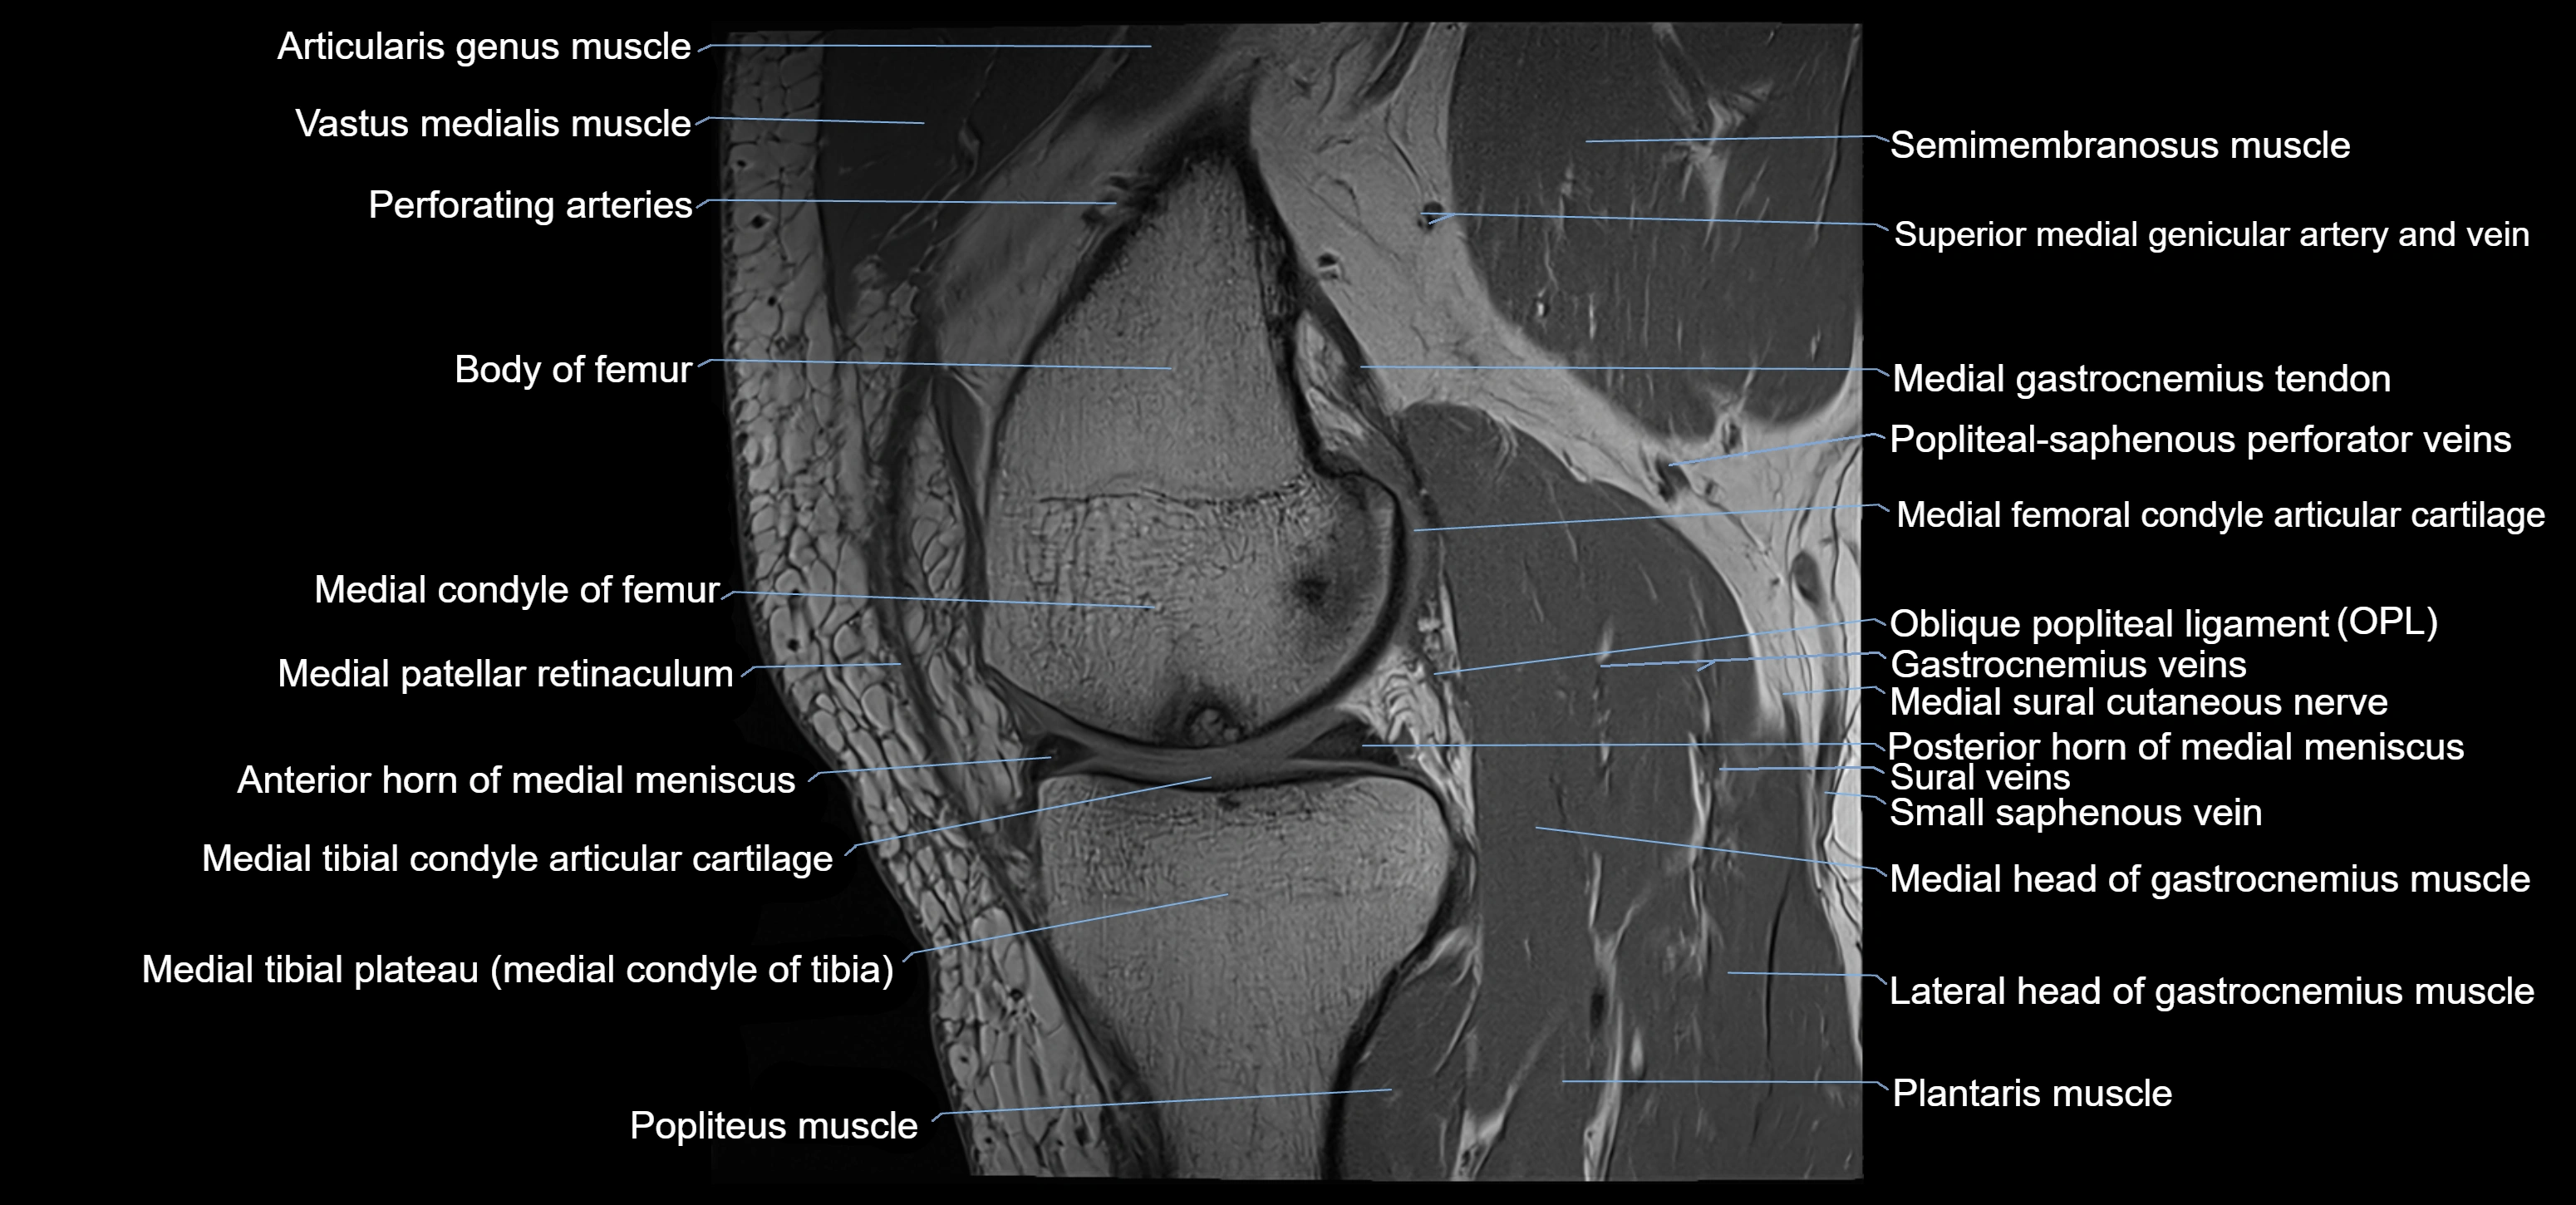

- Anterior horn of medial meniscus

- Medial condyle of femur

- Medial condyle of tibia

- Medial gastrocnemius tendon

- Medial head of gastrocnemius muscle

- Medial meniscus

- Medial patellar retinaculum

- Oblique popliteal ligament

- Plantaris muscle

- Popliteal artery

- Popliteal vein

- Popliteus muscle

- Posterior horn of medial meniscus

- Semimembranosus muscle

- Small saphenous vein

- Soleus muscle